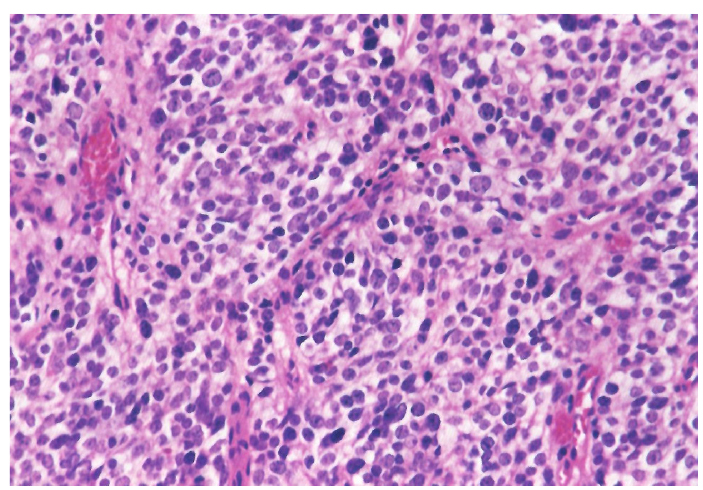

Поэтому при первичном гистологическом исследовании диагноз эстезионейробластомы был установлен только у 6 пациентов (66,6 %), у троих больных (33,4 %) были диагностированы другие формы злокачественного процесса, что не соответствовало клиническим проявлениям. Во всех случаях проводили иммуногистохимическое (ИГХ) исследование. ИГХ-исследование проводили на срезах с парафиновых блоков с использованием антител к Keratin.Pan (AE/AE3), CD45 (Cocktail), Synaptophysin (SP11), ChromograninA (SP12), CD56 (56C04), Ki-67 (30-9), p63 (7JUL)RTU, S100, INI1, CD99 (HO36-1.1). Также выполняли доставку с антителами к EMA (E29), TTF1 (8G7G3/1). В диагностических материалах была отмечена положительная экспрессия Synaptophysin, ChromograninA, CD56, Ki-67 (до 90% ядер), INI1 (рис. 2–6).

Рис. 2. Synaptophysin [SP 11] ×200

Рис. 3. Chromagranin A [SP 12] ×200

Рис. 4. CD 56 [56C04] ×200